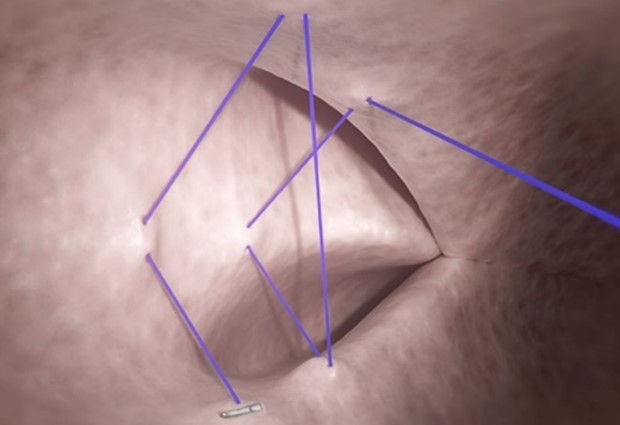

Foto de cierre del defecto

Cierres de defectos:

Cuando se trata de cerrar defectos, existen clips de solución rápida para problemas pequeños. Sin embargo, sus características radican en el tamaño y en la dependencia de la fijación mucosa. Para defectos más grandes se pueden requerir múltiples clips y pueden que no se realice el cierre completo de los defectos. Ingresa el Sistema de Suturas Endoscópicas OverStitch™. Este sistema te permite cerrar defectos mientras involucras tejido sano. Te brinda la ventaja de abordar defectos de cualquier tamaño. La sutura de espesor completo incorpora la capa muscular y consigue una construcción estable durante el proceso de cicatrización.